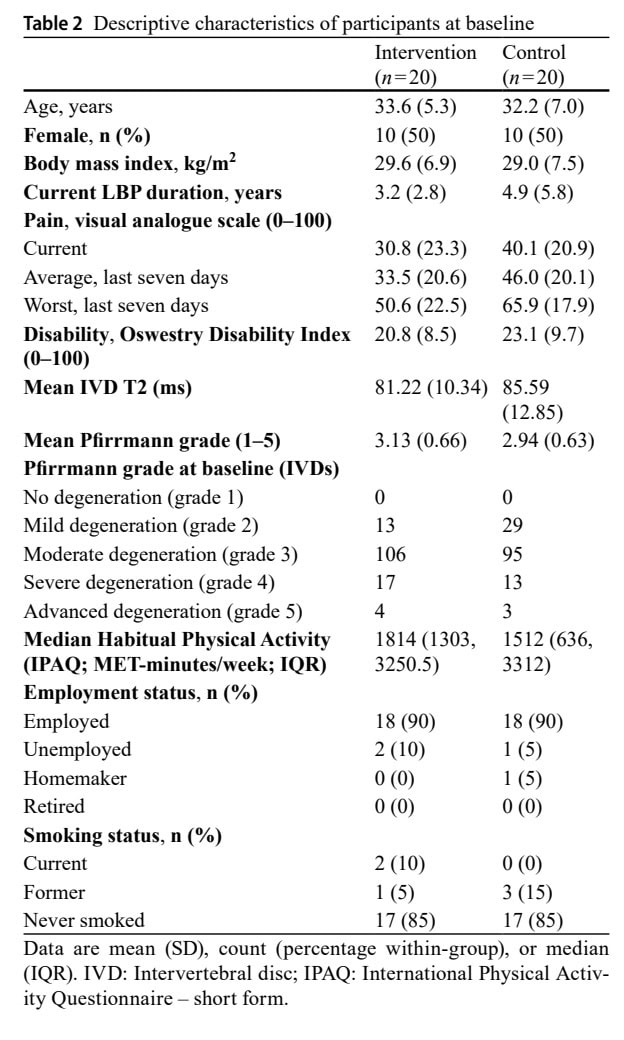

В исследование были включены 40 взрослых с хронической неспецифической болью в пояснице. Выборка была поровну разделена на мужчин и женщин.